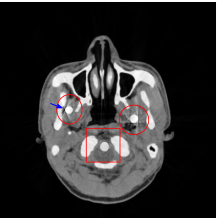

Figure 8 shows the reconstructed cerebral phantom from different methods. We highlight some regions with more distinct differences with red contours. Since the cerebral phantom contains more textures, it is more challenging than the NCAT phantom. The pros and cons of these methods are mostly the same as the previous example. However, we note that the reconstructed image from TV-FADM shown in Figure 8(e) has severe artifact, which is due to the well-known staircase artifact of TV regularization. We found that TV-FADM is relatively sensitive to the choice of its parameters. It is not easy to balance between sharpness of image features and metal artifacts reduction. The soft tissue around metal components is also not well preserved by the NMAR method as indicated by the blue arrow in Figure 8(d). Furthermore, the circled areas in Figure 8(d) show that there are still some artifacts around the metal. Same as the NCAT phantom, the proposed re-weighted JSR model has the best overall performance. Notice that the intensity of metals in Figure 8(d) and 8(f) seems lower than the rest of the reconstructed images. This is because we set the intensity of the metal components in the segmentation with the same mean value as that of bones. Increasing the value of metal components of can increase the intensity of metals in the reconstructed images, whereas it also introduces more artifacts around the metals.